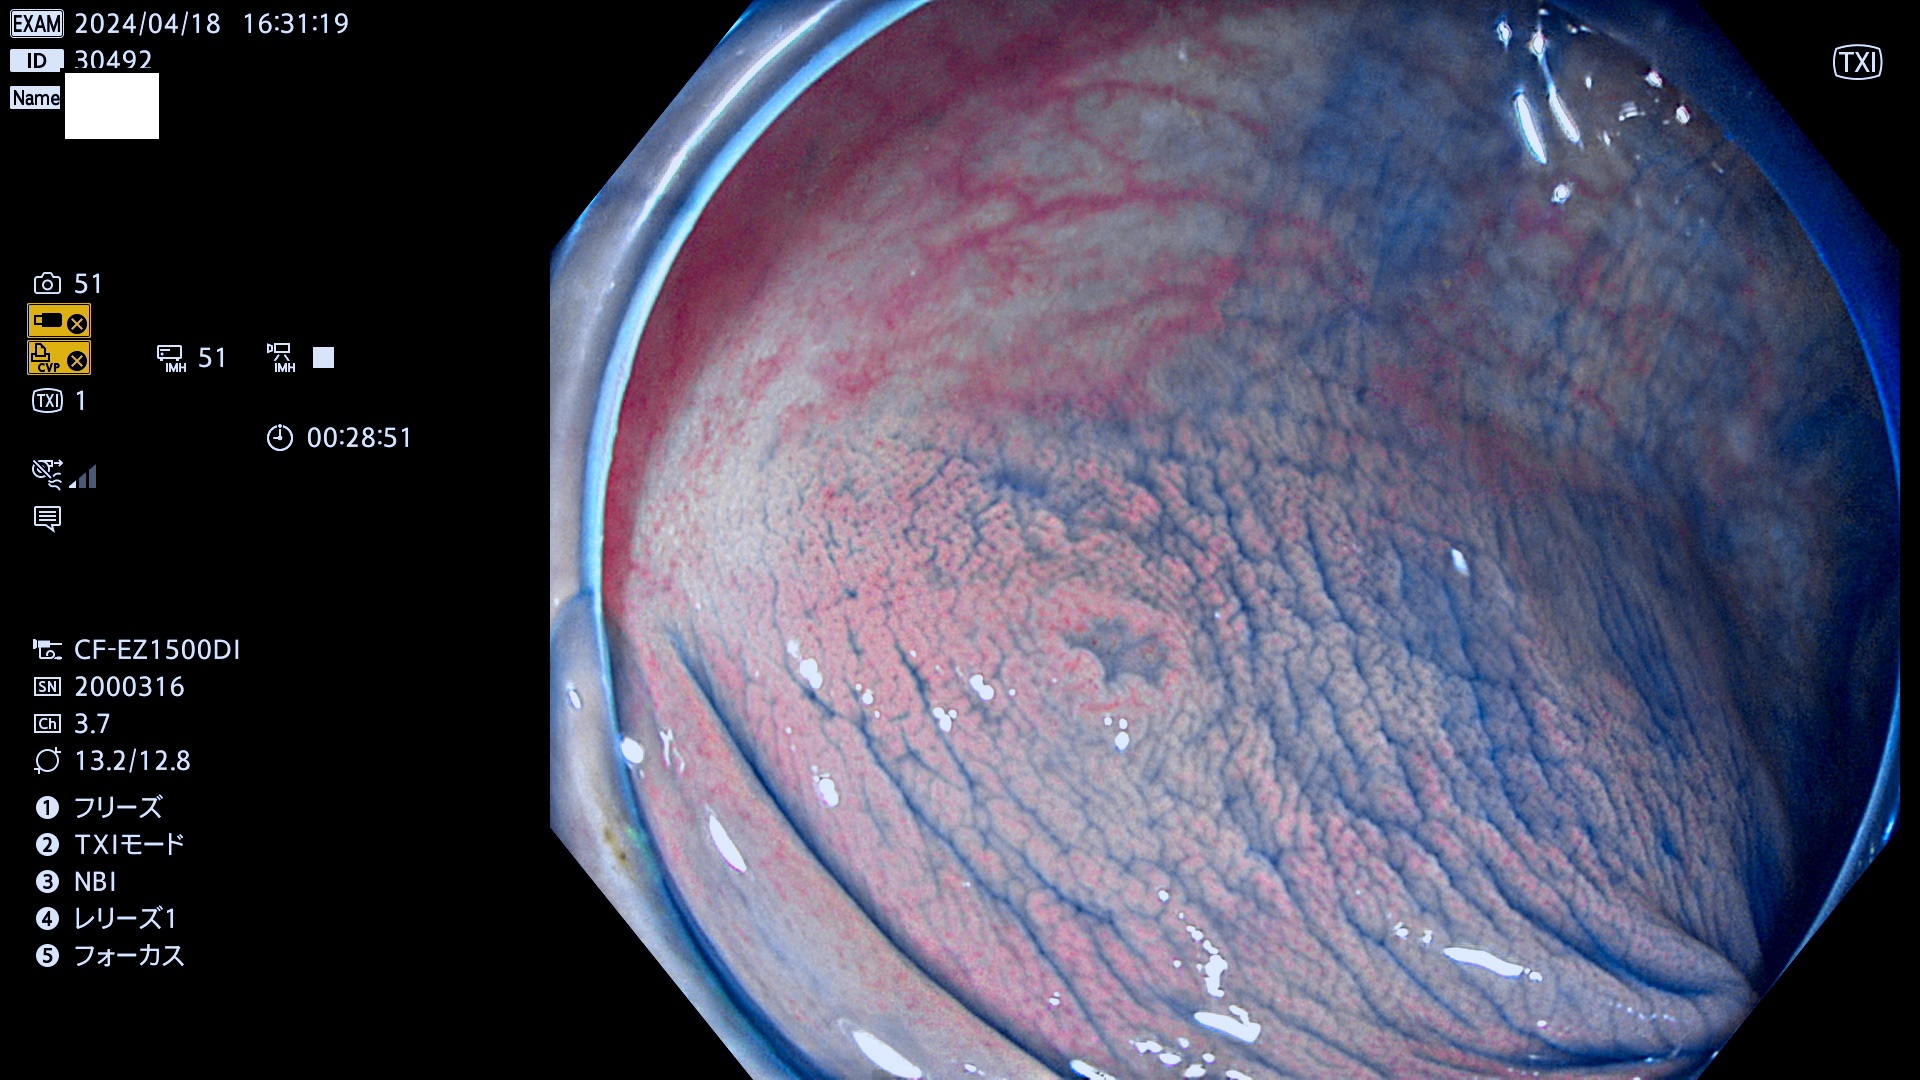

表面型腺腫(Flat Adenoma)の中で、完全に平坦な物をUb、陥凹している物をUcと呼びます。平坦隆起型(Ua)よりも、発見が難しく危険な病変です。

毎週の検査(木・金・土・日)に発見されたUb、Uc型・腺腫を、その週の日曜の夜にUPし1週間、提示します。

抽出の対象期間 2024年4月18日〜4月21の4日間(40件の検査)3件 (3/40=8%)